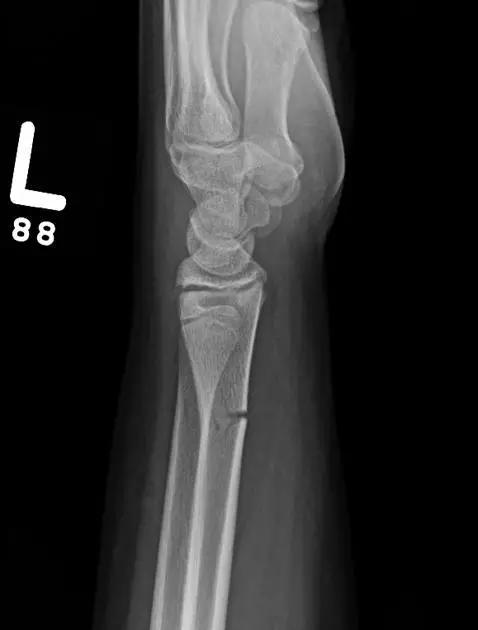

2. Colles 骨折

桡骨远端骨折,伴有桡骨远端向背侧的移位,可以有或没有尺骨干的骨折。具有这几个特征:背侧粉碎、向背侧成角、向背侧移位且挠骨短缩的关节外骨折。

典型 colles 骨折,枪刺样、餐叉样畸形